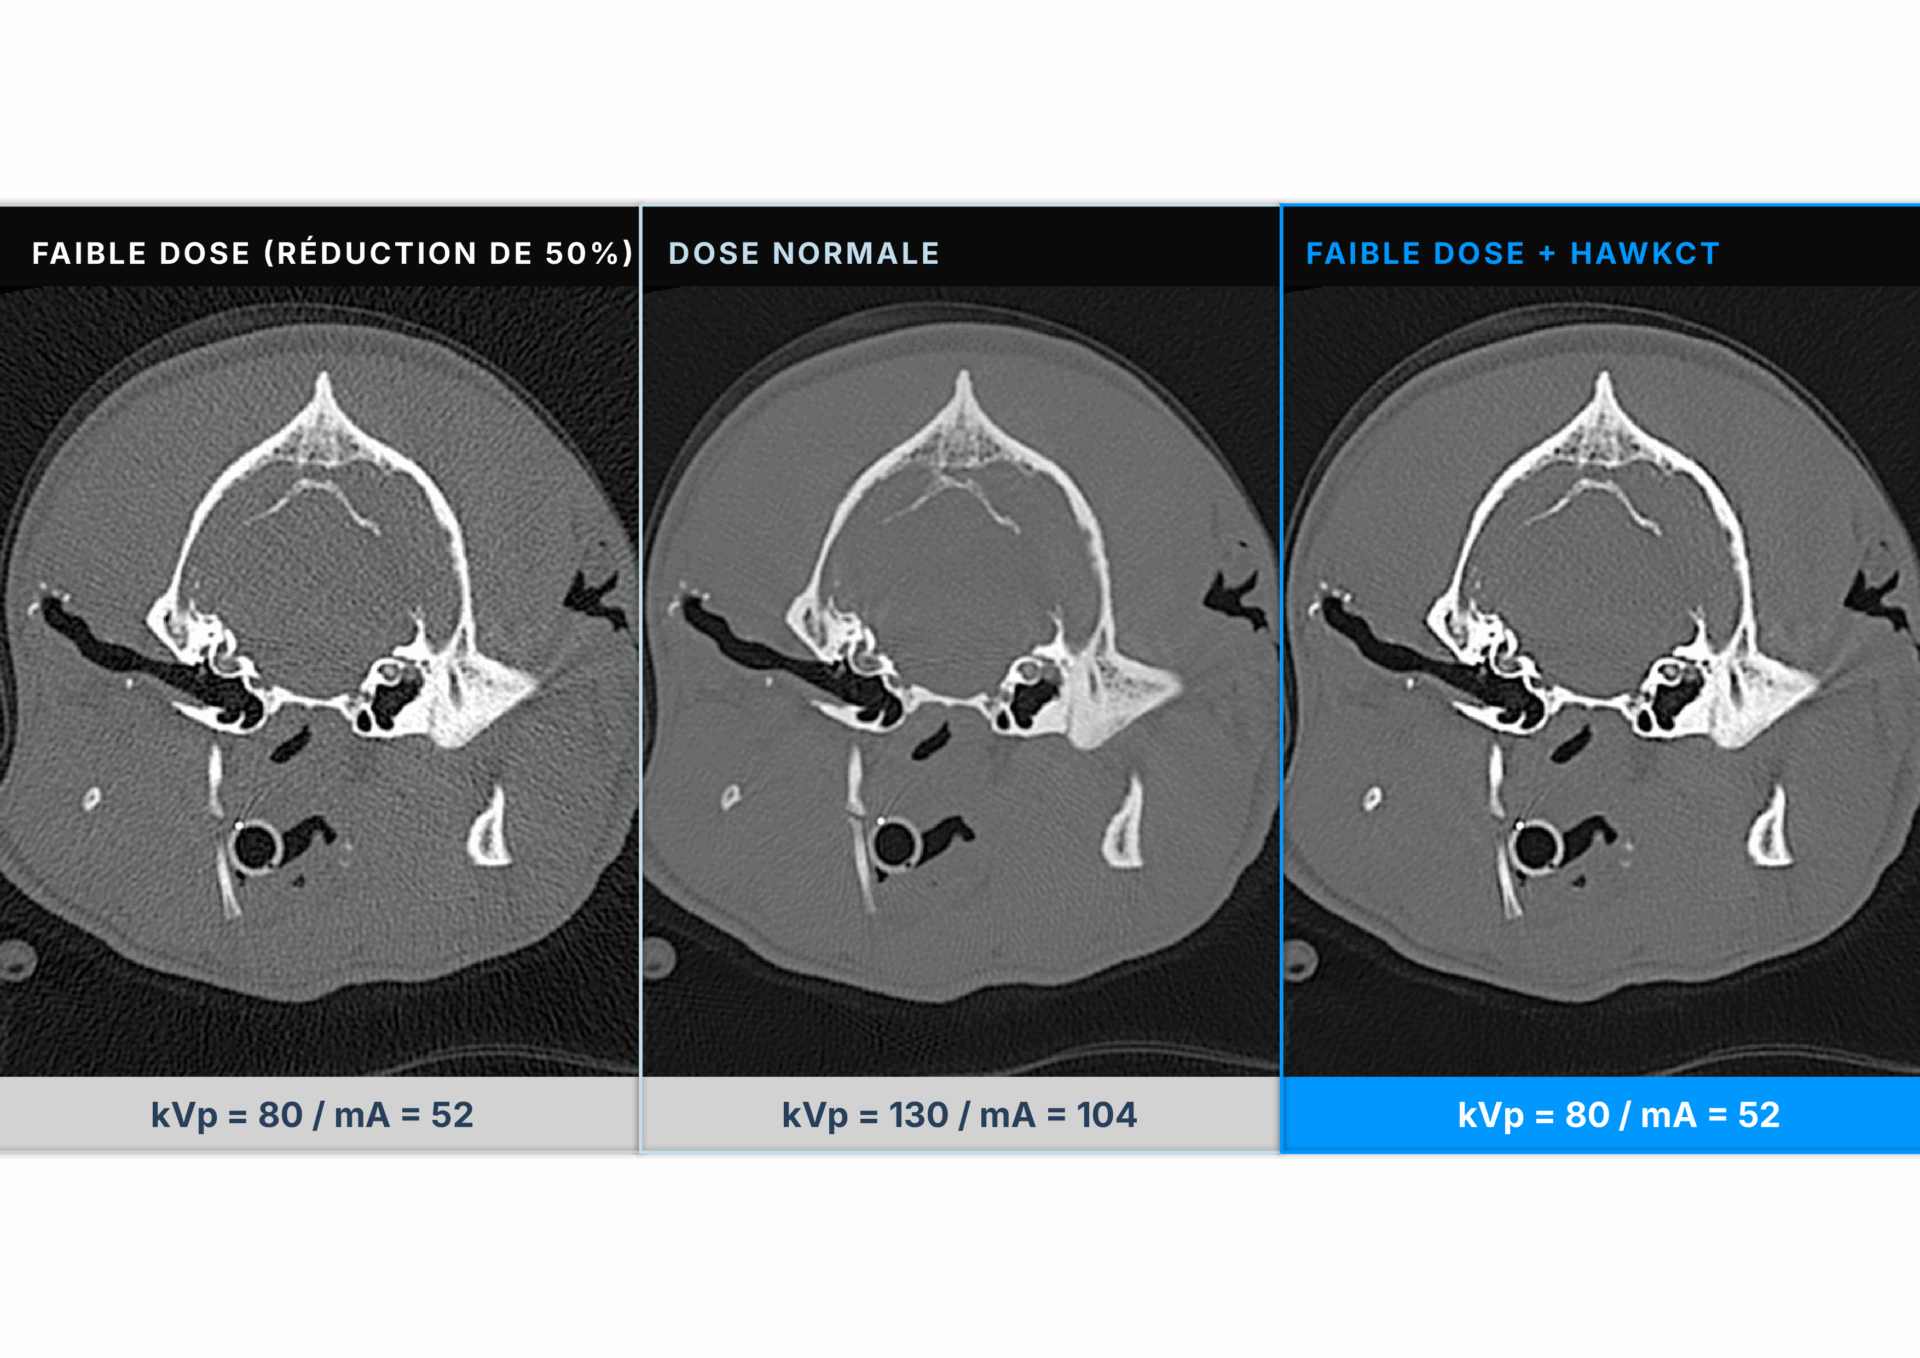

HawkCT est un algorithme de deep learning appliqué au scanner vétérinaire, conçu pour définir un nouveau standard en imagerie. Il offre des examens plus rapides, une réduction de l’exposition aux radiations et une meilleure qualité d’image.

HawkCT optimise les flux de travail, réduit les coûts énergétiques et de consommables, et s’intègre parfaitement à tout système de scanner. En réduisant le temps d’anesthésie et en diminuant la dose de radiation, il améliore la sécurité des patients tout en maintenant la précision diagnostique.

Sa reconstruction avancée renforce le contraste et la résolution, garantissant une qualité d’image constante sur toutes les séquences. Exclusivement conçu pour les vétérinaires, entraîné et validé sur des données animales, HawkCT permet aux cliniques d’accéder à une imagerie scanner plus rapide, plus sûre et plus durable.